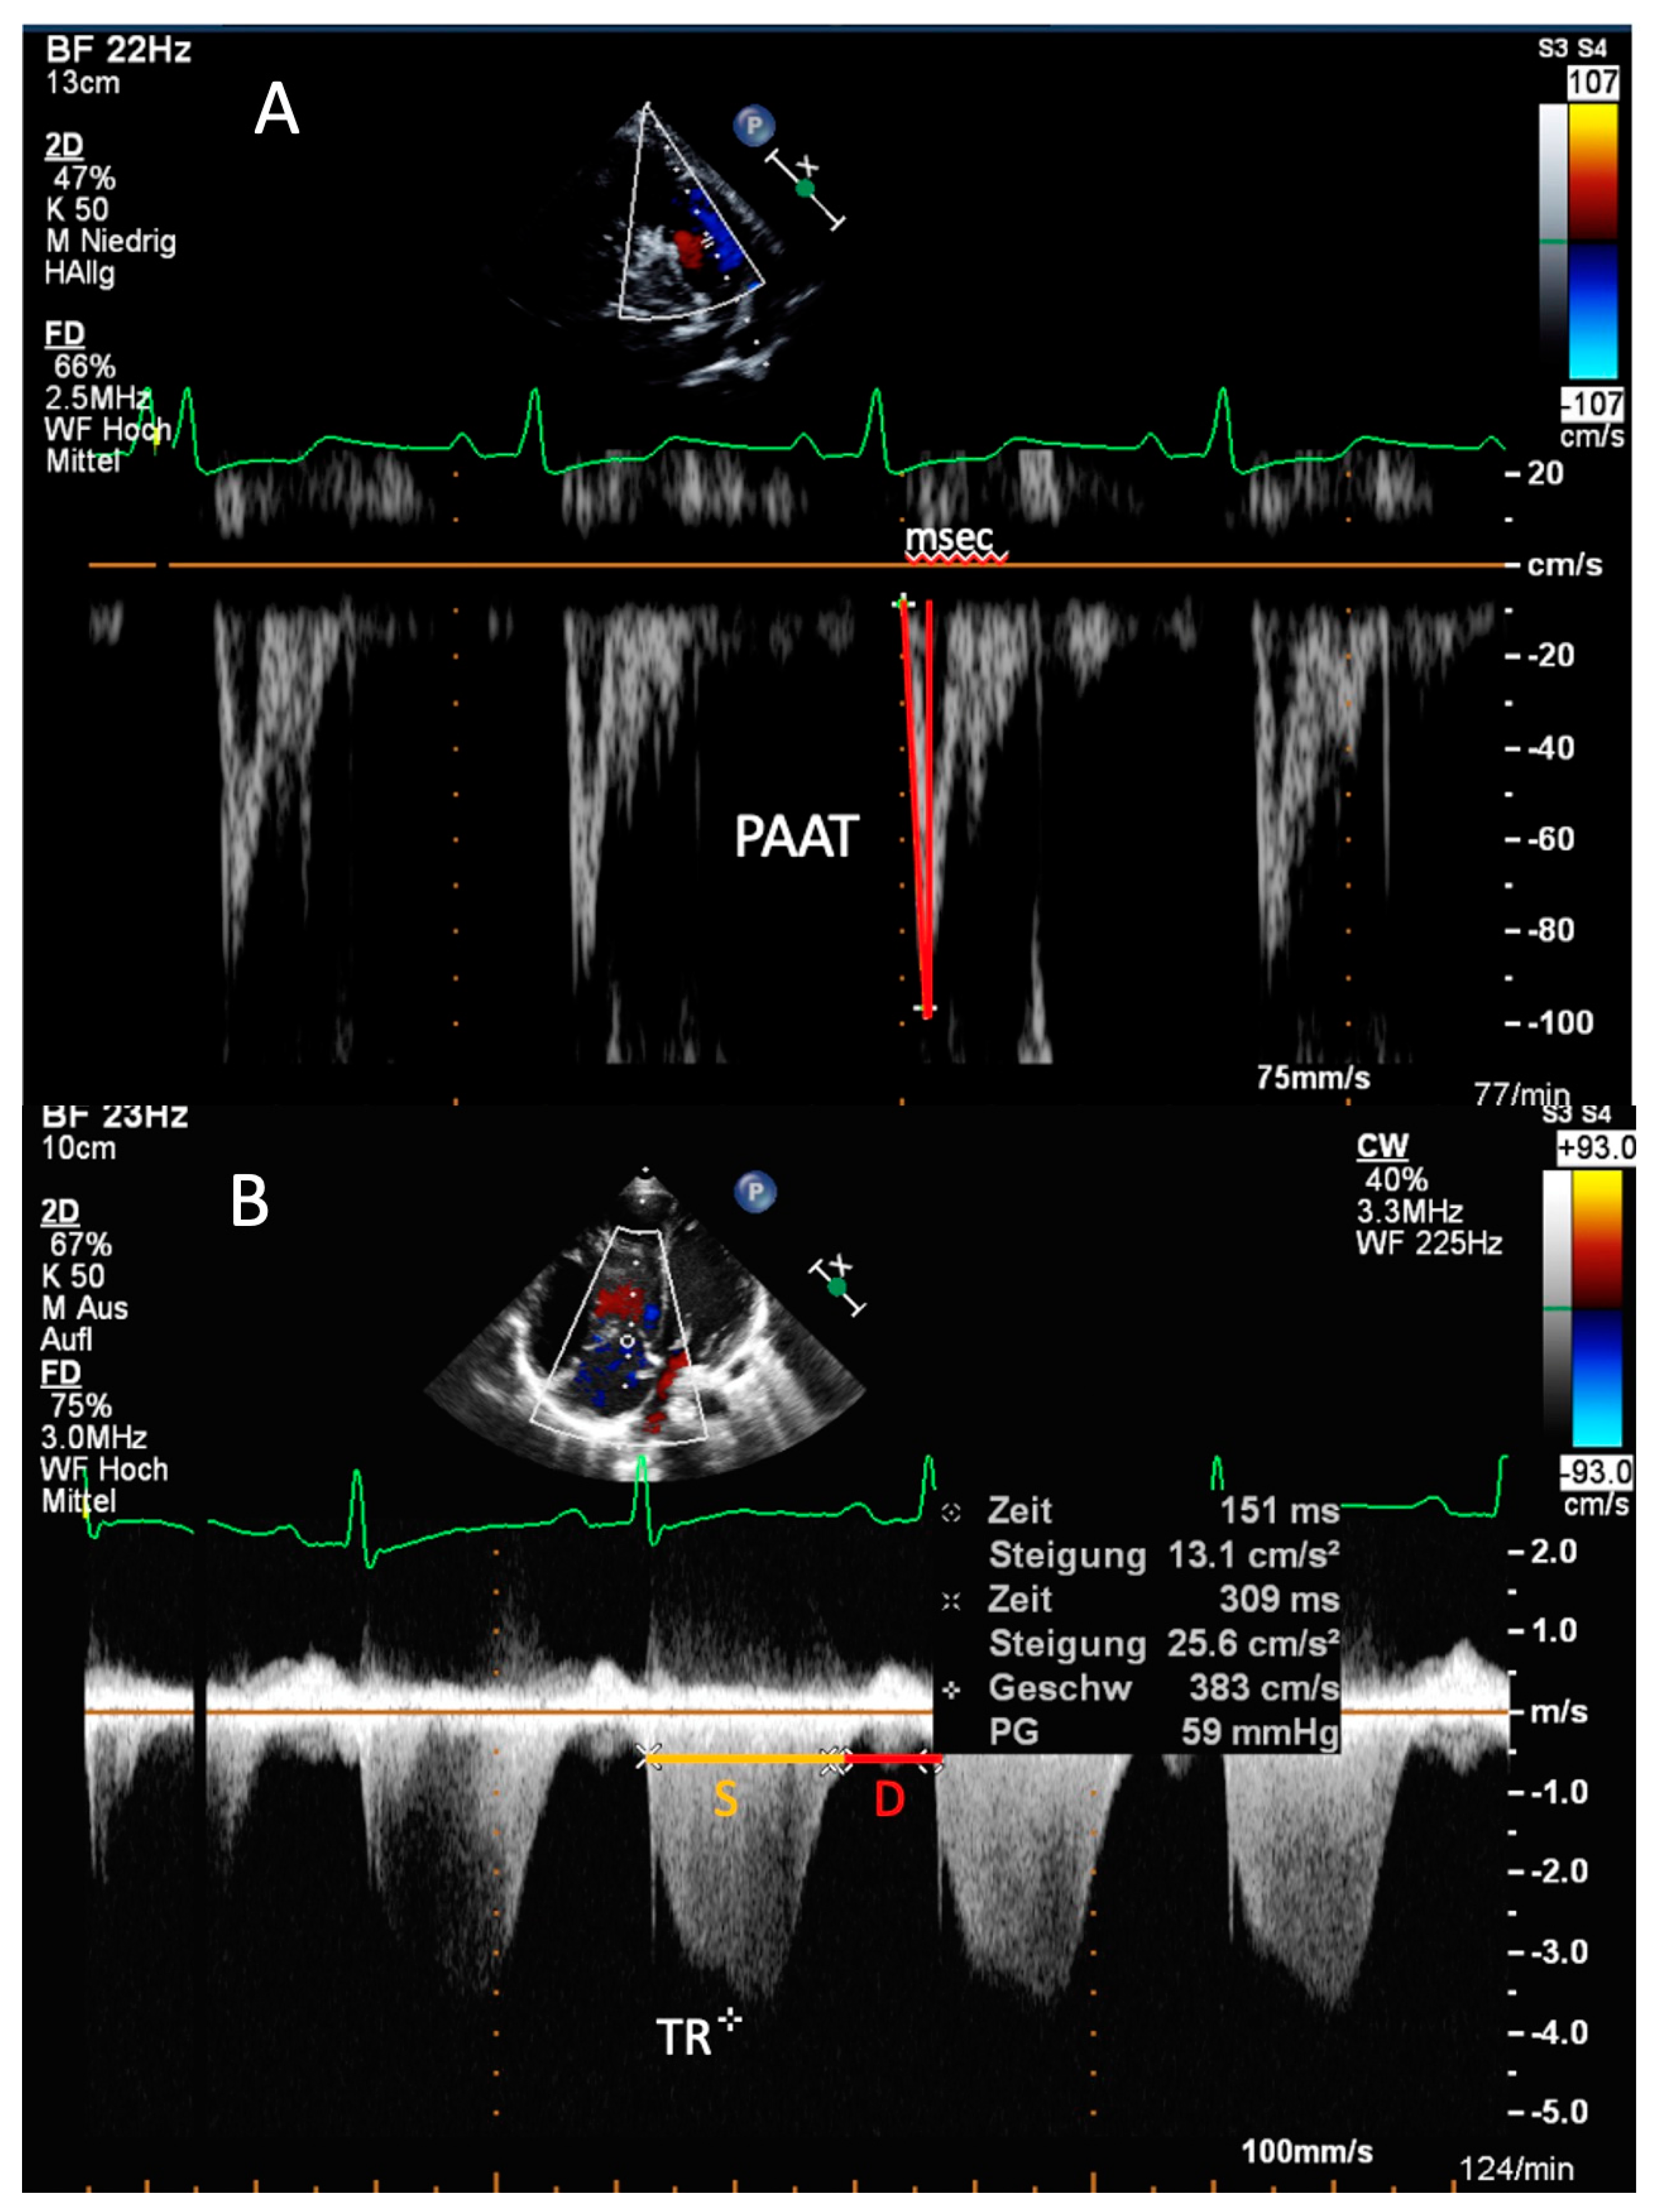

| PAAT | Can be measured in most of PH patients; PAAT < 100 ms in adults—PH is likely; Existing reference values in children | Possible pulmonary valve artifacts; Heart rate dependent (PAAT/RVET ratio is less dependent on age, BSA and heart rate) |

| S/D ratio | S/D duration ratio > 1.4—PH is likely; Geometric independent ratio | Requires presence of defined TR onset/end; Heart rate dependent parameter |